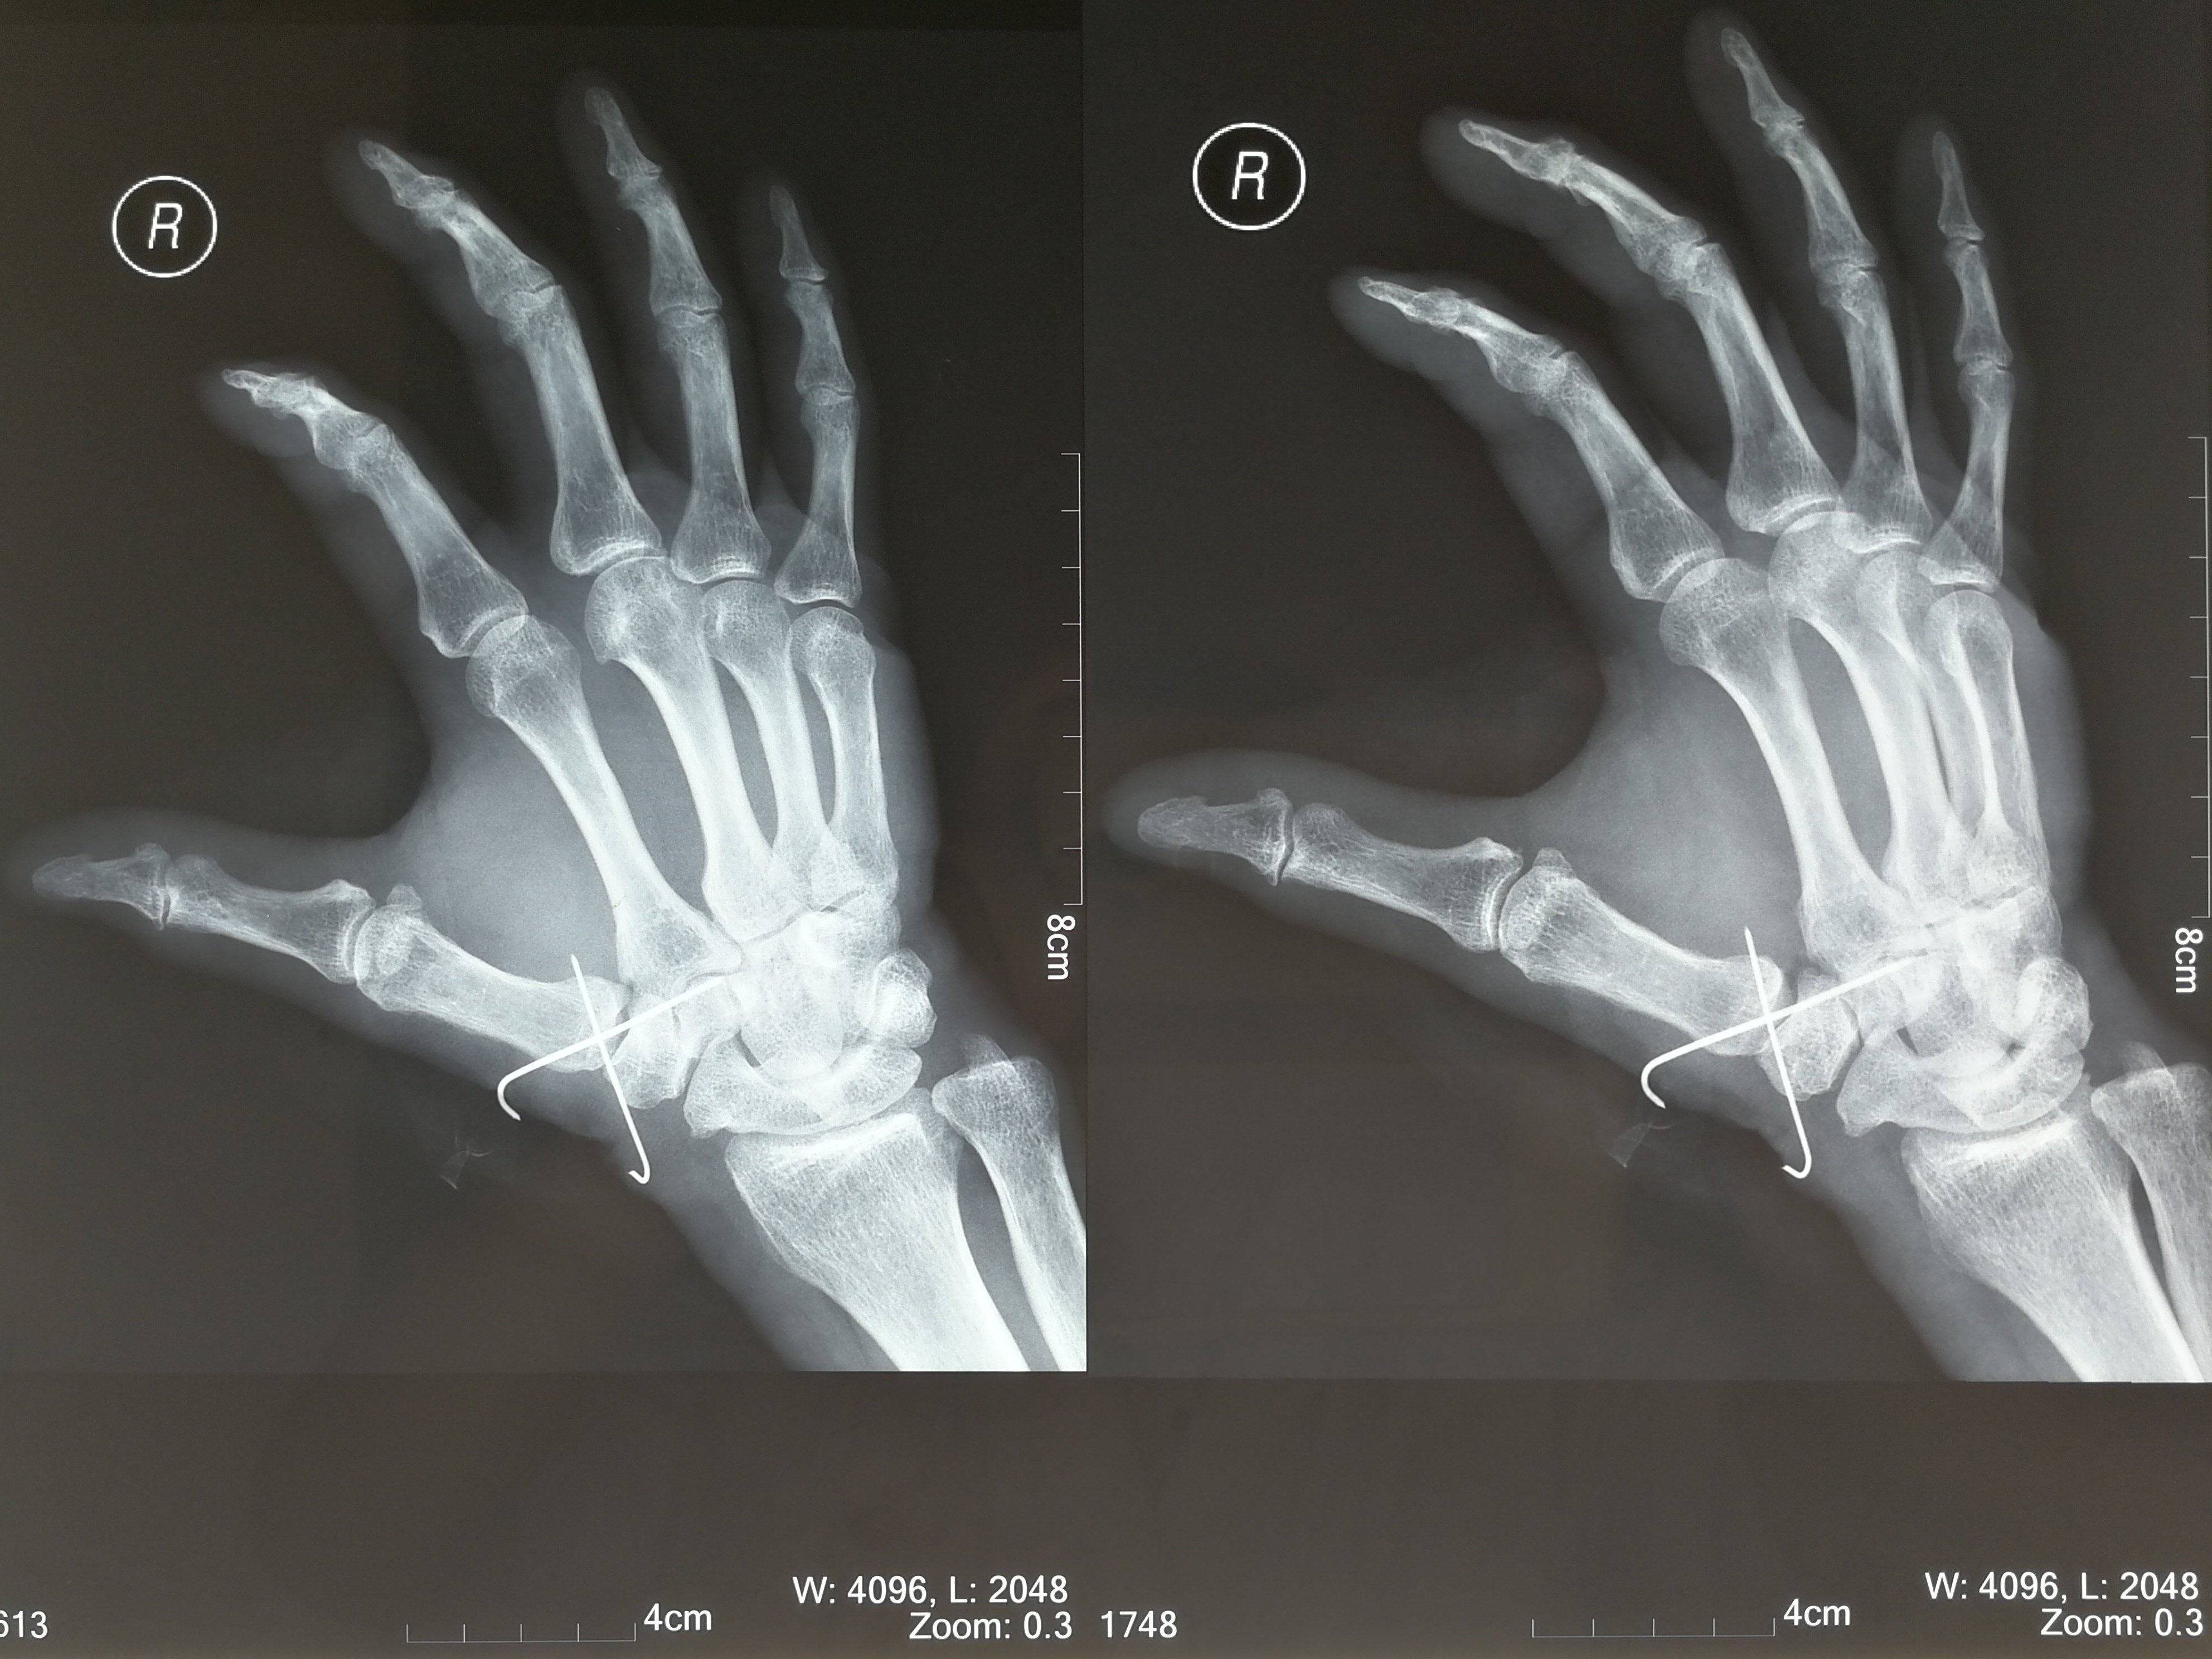

本耐氏bennett骨折即第一掌骨基底部骨折伴脱位

第一掌骨基底部骨折

第1掌骨基底骨折1例 请各位老师指点